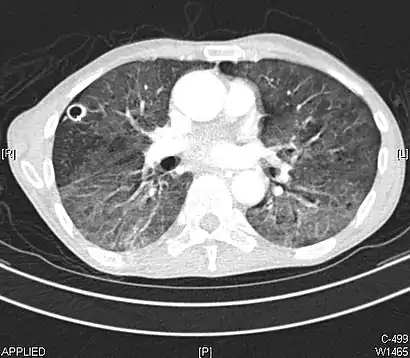

CT showing diffuse ground-glass opacities in periphery of both lungs in patient with COVID-19.